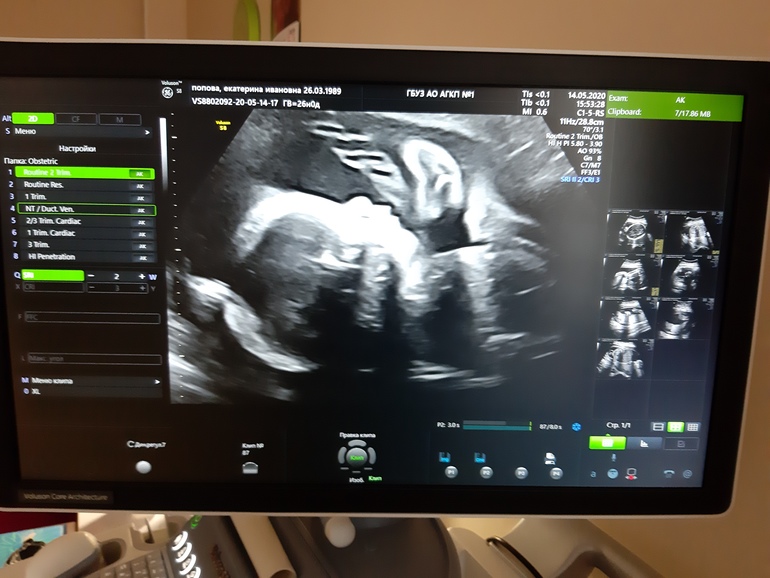

УЗИ 25+3

На узи все кисты в голове рассосались, собственно из-за чего это узи мне и сделали, так как в 18 недель там высмотрели кисты и на контроль поставили. Ну и хорошо, в этот раз все полностью в норме и никаких вопросов нет) я рада! Ещё раз посмотрела на свою конфетку, до нашей встречи все меньше времени остаётся